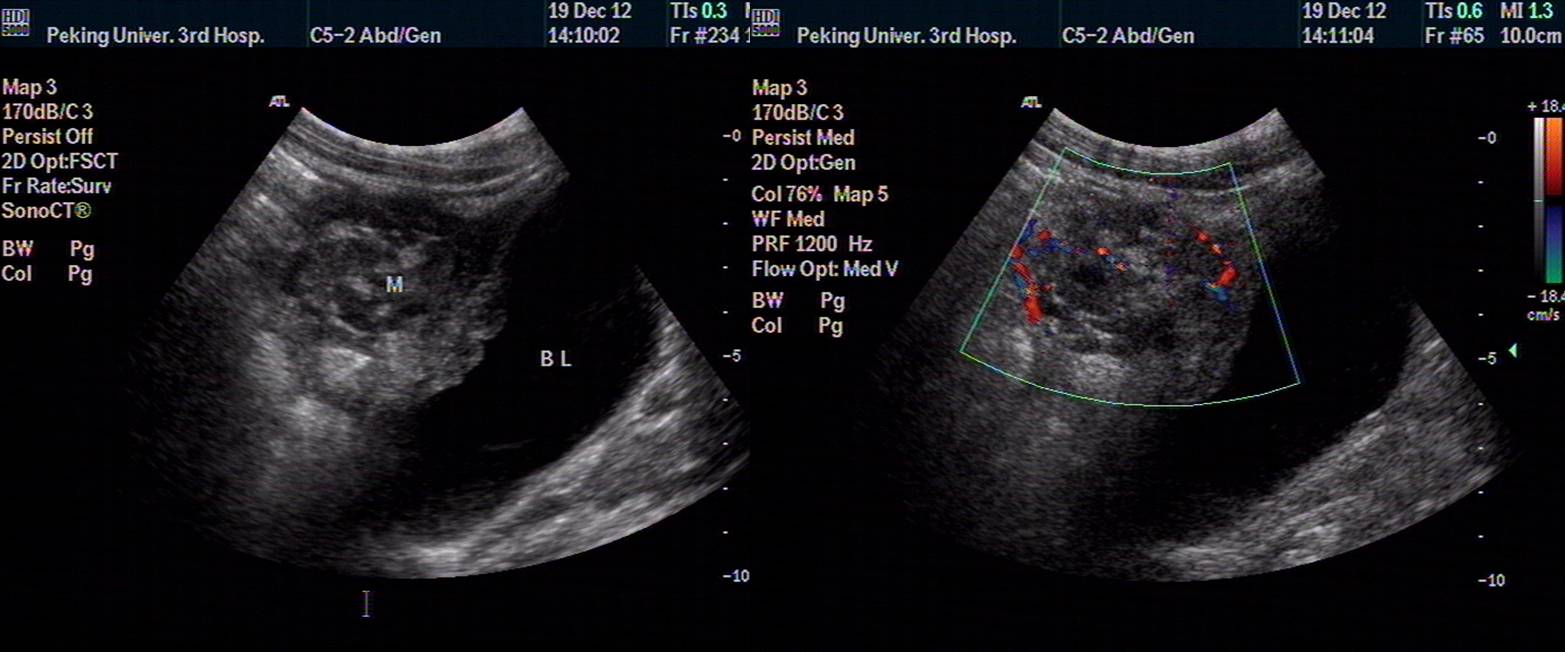

2012.11.22 US:膀胱上方可见大小约5.9*4.9cm不均质中低回声,边界不清,其内可见团块状强回声,CDI:内可见少量血流信号,吸气时该包块与腹壁粘连。下腹部肠间可见少量积液。

2012.12.19 US复查,同前。